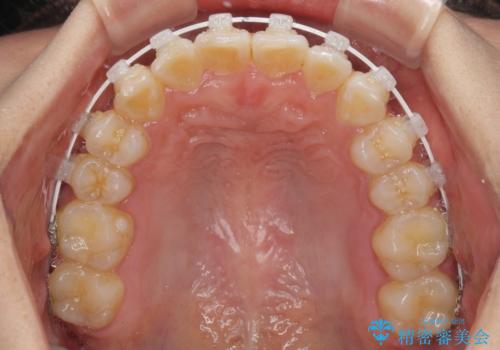

- 上下のデコボコと前歯のクロスバイトを改善したいとのことで来院された患者様です。

極力短期間で治療したいとのことで、ワイヤー装置による矯正治療を行うこととしました。

お住まいが遠方であったため、マウスピースによる矯正治療も提案しましたが、ご自身でのマウスピースの管理の面倒くささと、なるべく早く治療を終えたいとのことで、ワイヤー矯正を選択されました。